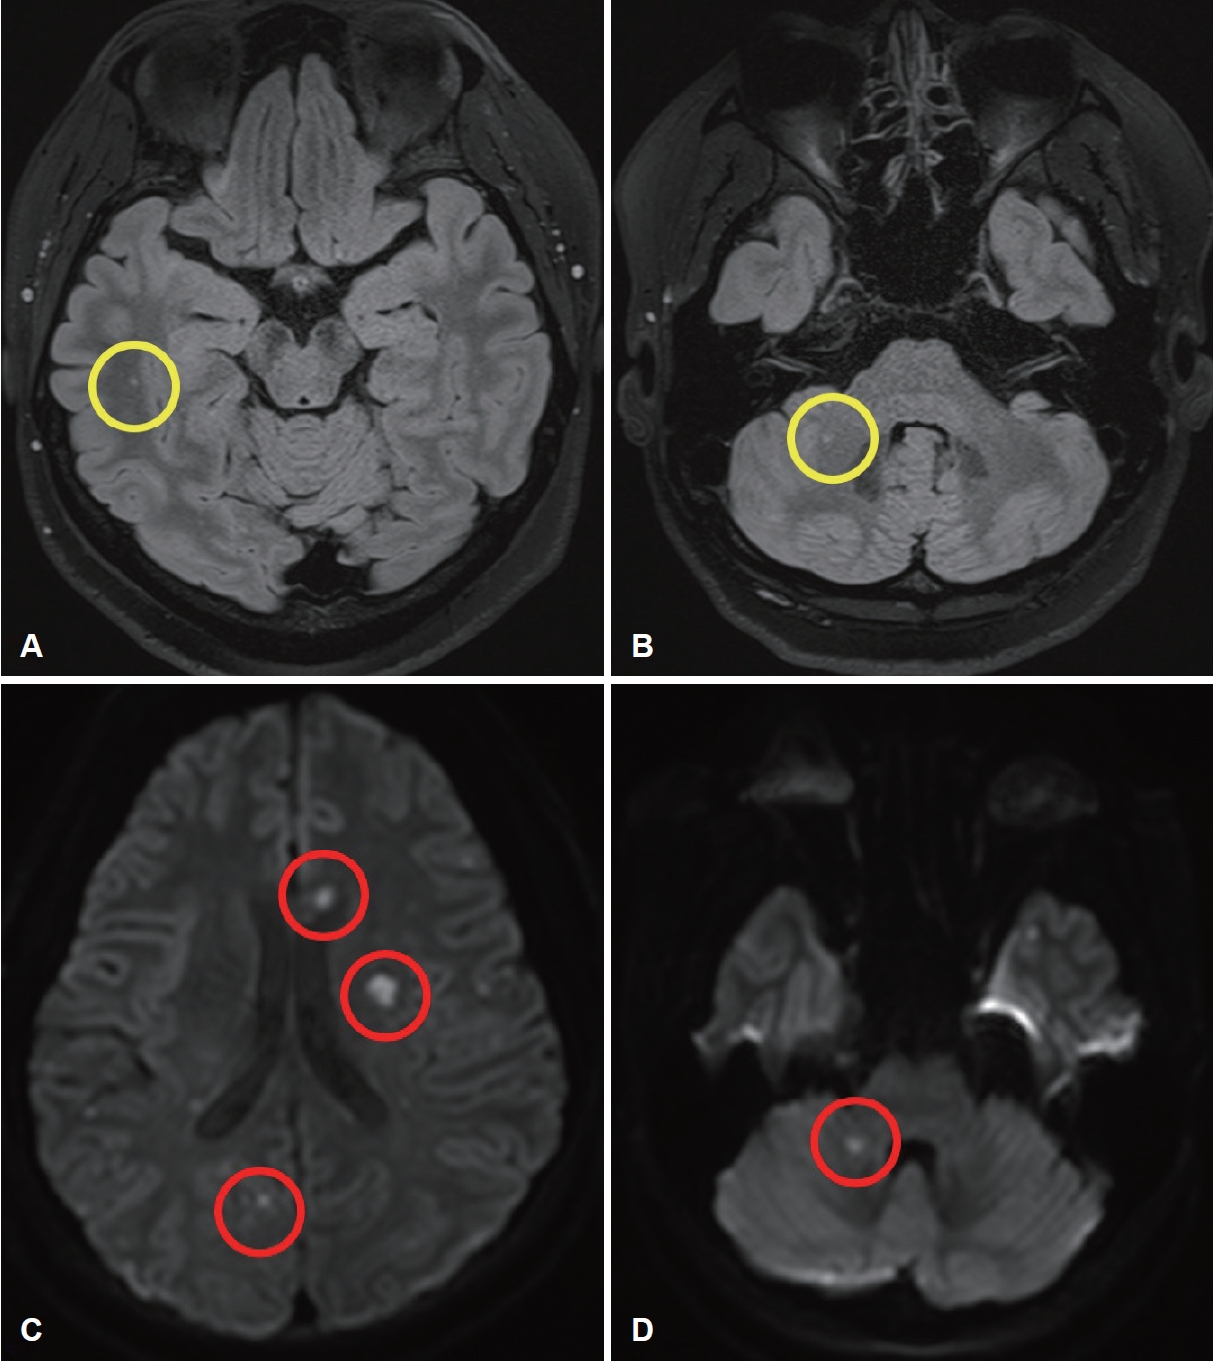

본원 내원 당시 환자는 고실 내시경 검사에서 양쪽 귀는 정상이었으며 현훈 양상의 어지럼증을 보였으나 명확한 안진은 없었으며 안면 마비도 없었다. 순음 청력검사상 우측 중도 난청 소견을 보여 어지럼증을 동반한 돌발성 난청 진단하에 본과에 입원했다(Fig. 2A). 입원 중 시행한 내이도 자기공명영상 촬영상 우측 측두엽과 좌측 후두엽 및 양측 소뇌 실질에 다발성의 미확인 밝은 물체(unidentified bright object)가 보였다. 환자는 5일간 경구 및 정맥 내 스테로이드 투약 후 퇴원했으나, 10일 후 갑자기 말이 어눌해지며 어지럼증이 심해지고 자발성 상방안진(upbeat nystagmus)과 함께 스큐편위(skew deviation)가 보여 확산강조 자기공명영상촬영(diffusion-weighted image) 시행 후 우측 소뇌 경색 진단하에 본원 신경과 입원하였다(Fig. 3A and B). 경동맥초음파상 특이소견은 없었으나, 심초음파상 심방중격결손이 발견되어 항응고제를 변경하고 심방중격결손 폐쇄 시술 예약 후 퇴원하였다.

퇴원 3일 후 정상이었던 좌측 귀에서도 심도 난청이 발생하고, 우측 귀는 고도 난청으로 악화되는 양상을 보여 본원 신경과로 재입원하였다(Fig. 2B). 재시행한 자기공명영상촬영에서 양측 대뇌 실질 및 우측 소뇌 경색의 진행 양상이 확인되었다(Fig. 3C and D). 또한, 진단검사에서도 단백질 S의 항원과 활동성이 기준치 이하로 저하된 것을 확인할 수 있었다. 이에 항응고제 추가 및 심방중격결손 폐쇄 시술 후 퇴원하였다. 퇴원 후 외래 통해 추적 관찰했을 때 의식 저하가 생기거나 말이 어눌해지는 등 추가적인 뇌경색 증상은 발생하지 않았으며 어지럼증도 소실되었다. 양측 난청에 대해서 구제요법으로 고실 내 스테로이드 주입술을 수차례 시행했으나 청력 호전은 이루어지지 않았다(Fig. 2C). 언어평가 시 보청기를 착용한 상태에서 보기가 주어지지 않았을 때(open set) 단음절어는 16.6%, 일상문장은 4%로 언어식별능력이 저조했다. 청력 호전이 없으며 보청기 착용 후에도 일상생활이 힘들 정도로 언어 식별이 되지 않아 좌측 인공와우 수술 계획하였다. 수술 전 시행한 청성뇌간유발반응상 좌측 제 V파가 보이지 않고 우측 80 dB HL에서 제 V파가 보였으며, 청성지속반응검사에서는 순음청력검사와 비슷한 양측 심도 난청 소견을 보였다.